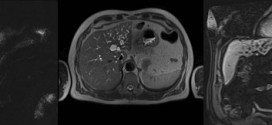

COLANGIOCARCINOMA INTRAHEPÁTICO

El Colangiocarcinoma intrahepático. Tumor maligno en general de las vías biliares. El sistema para drenar la bilis, incluye los conductos o vías extrahepático, conductos biliares intra y la vesícula biliar. Son como una red de cañerías, llamados conductos que están conectados con la vesícula biliar, el intestino delgado y el hígado. El Colangiocarcinoma este tumor se ubica o desarrolla en …